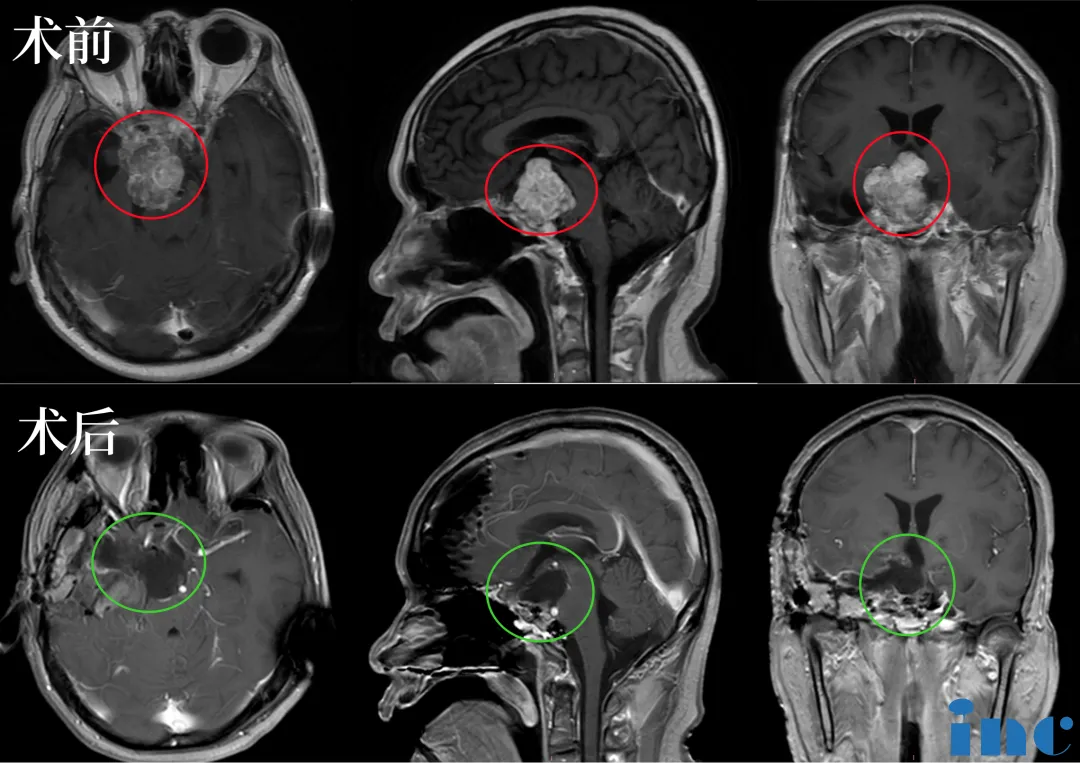

术前术后对比:手术顺利,术中将鞍上鞍内、海绵窦区、三脑室肿瘤切除

▼2023年8月初在苏州大学附属第四医院(苏州市独墅湖医院)为一名6岁脊索瘤患儿实施了高难度示范教学手术。6岁的林林因头疼,行走不稳等症状被诊断为颅底脊索瘤。肿瘤位置复杂,体积巨大,明显压迫脑干,林林在国内接受了第一次手术,部分减少肿瘤的体积。然而,剩下的肿瘤仍然很大。林林父母走投无路之际从国内神外专家得知福洛里希教授即将来华的消息,果断进行了远程咨询。幸运的是他们如愿得到了教授充满希望的回复并决定请他进行第二次手术。从远程咨询到成功手术仅10天,术后10天顺利出院。成功术后7个月,福教授来华进行学术沙龙交流期间。林林妈妈带着他亲自来到上海INC办公室,亲自感谢这位拯救了孩子的世界神外大咖,并进行术后随访。

▼术前术后影像对比